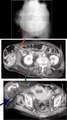

HERNIAS DE PARED ABDOMINAL